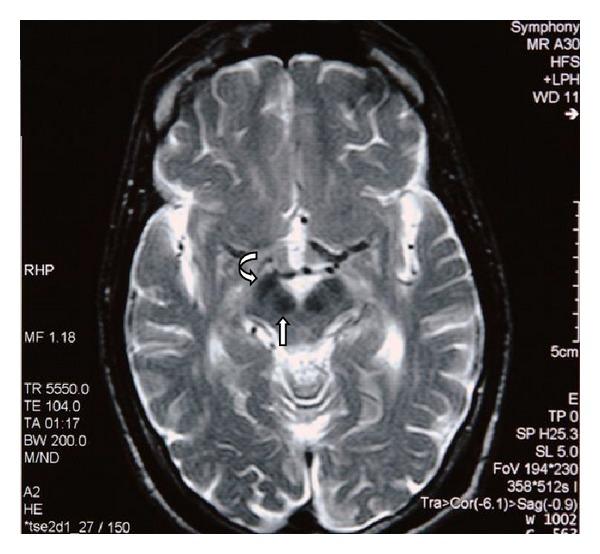

A 29-year-old male petrol station pump attendant was admitted with ataxia and clinical evidence of a sensorimotor polyneuropathy which developed over the preceding 3 months. He had cognitive dysfunction, hearing loss, and cerebellar clinical abnormalities that came on slowly over the three years. He had a fifteen-year history of sniffing mostly glue, occasionally paint thinners, and, in the recent two years, gasoline. Magnetic resonance brain imaging showed abnormalities of the cerebral cortex, cerebral white matter, corpus callosum, hippocampus, brainstem and cerebellar atrophy, hypointensities of basal ganglia, red nuclei, and substantia nigra as previously described in toluene sniffing. Abstinence for six months led to partial clinical improvement. Clinicians need to be aware of this preventable entity which has peculiar radiological findings which are being increasingly accepted as typical.

一名29岁的男性加油站油泵服务员因共济失调以及在前3个月内出现的感觉运动性多神经病的临床证据而入院。他有认知功能障碍、听力丧失和小脑临床异常,这些症状在3年里逐渐出现。他有15年的吸入史,主要是胶水,偶尔是油漆稀释剂,近两年来还吸入汽油。磁共振脑成像显示大脑皮质、脑白质、胼胝体、海马体、脑干和小脑萎缩,基底神经节、红核和黑质低信号,正如先前在甲苯吸入中所描述的那样。禁欲6个月导致临床症状部分改善。临床医生需要意识到这种可预防的疾病,它有独特的放射学表现,并且越来越被认为是典型的。